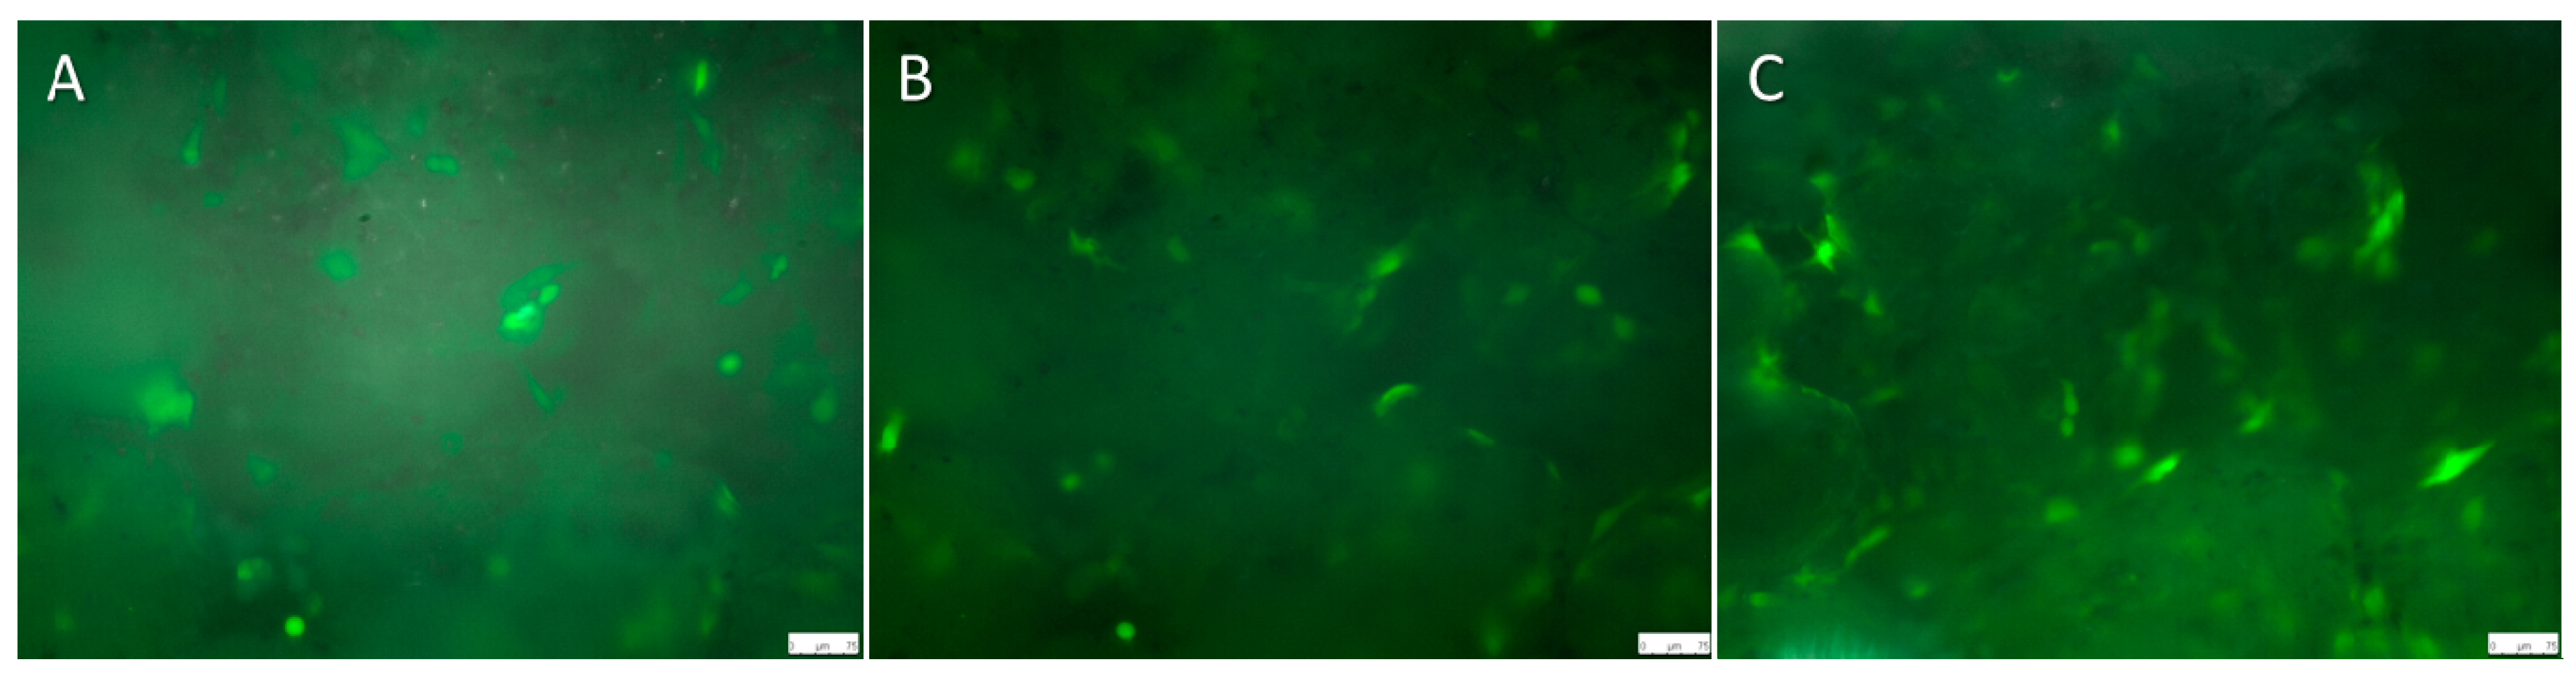

2.3. Live Cell Imaging (LCI) of Magnesium Hybrid Construct Compared with the Titanium Implant Coated with Polycaprolactone (PCL) Seeded with Green Fluorescent Protein (GFP)-Osteoblast

2.5. LCI of Osteoblasts Seeded on Magnesium PCL and Titanium PCL Implants

4.6.1. LCI of Titanium Implant Seeded with GFP-Osteoblast

4.6.2. LCI of Magnesium Hybrid Construct and Magnesium PCL Implant Seeded with GFP-Osteoblast